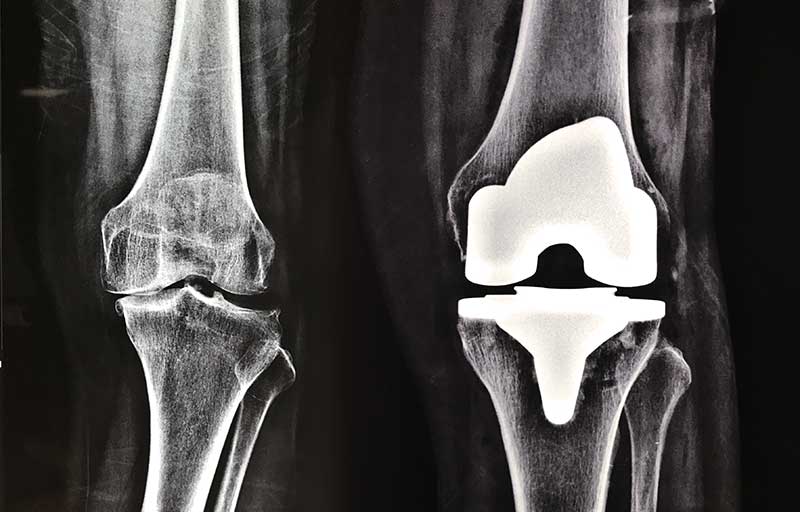

Operasi penggantian sendi lutut adalah operasi yang dilakukan untuk mengganti sendi lutut yang telah mengalami kerusakan akibat pengapuran sendi dengan sendi lutut buatan. Pengapuran sendi paling sering mengenai sendi lutut sehingga operasi penggantian sendi lutut merupakan operasi penggantian sendi yang paling banyak dilakukan.

Operasi penggantian sendi lutut bermanfaat menghilangkan nyeri sendi akibat pengapuran sendi dan memperbaiki bentuk lutut yang bengkok menjadi lurus kembali.